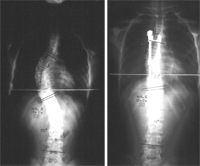

La palabra escoliosis proviene del griego y significa curvatura lateral de la columna vertebral. Esta enfermedad se manifiesta clínicamente por la curvatura lateral de la columna, acompañada por la rotación de las vértebras afectadas.¿Por qué surge la escoliosis?

La cifosis de carácter leve se trata con medidas conservadoras: ejercicio físico adecuado, rehabilitación y controles periódicos. Cuando es de grado alto, en casos de dolor y de deformidad intolerable, se recurre al tratamiento quirúrgico.

La cirugía se indica en muy raras ocasiones y se hace en curvas mayores de 80º.